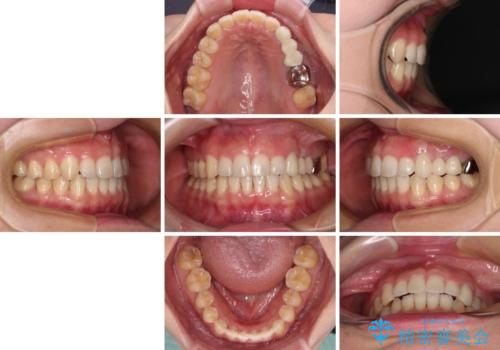

捻れた前歯と銀歯のブリッジを治したい ワイヤー矯正とオールセラミックブリッジ

- 上下前歯のデコボコと銀歯のブリッジを気にして来院された患者様です。

装着されているブリッジを切断して矯正治療を行うことや、手間をかけずに早めに治療を終えたいとのことで、目立たないワイヤー装置による矯正治療を行うこととしました。

矯正治療後には切断したブリッジをオールセラミックブリッジに置き換えることとしました。

矯正治療中に上下前歯が接触しない時期があり、咬み合わせ改善のために期間がかかるのではないかと懸念されましたが、結果的には補綴治療も含めて1年以内の短期間で終えることができました。